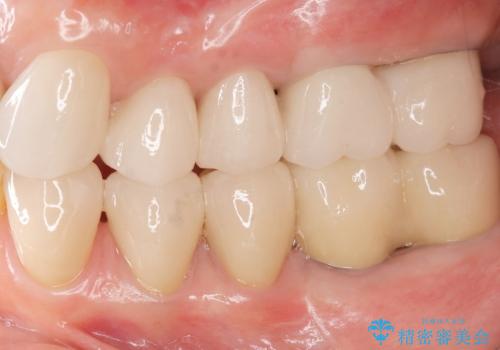

不適合やすり減ったクラウンを全て除去し、虫歯を丁寧に除去したのち精密なセラミック治療を行いました。

しっかりと調整された咬合関係と、見た目の改善に大変喜んでいただくことができました。